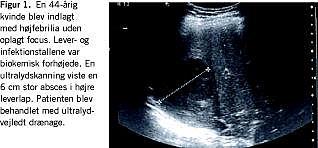

Som eksempler på positive ultralydfund var abscessus hepatis, pancreatitis acuta, metastaser, hydronefrose, tumorer, pyelonefritis og cholecystitis (Figur 1 ).